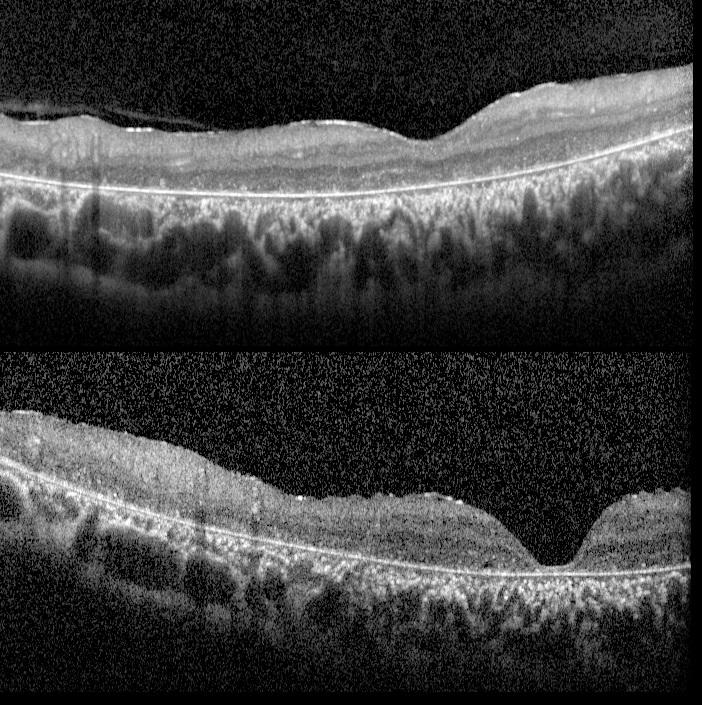

OCT showed severe photoreceptor and RPE atrophy.

OCT of severe ABCA-4 retinopathy